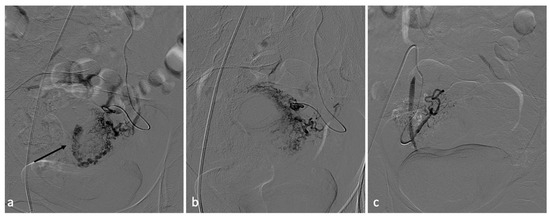

Figure 5.

Pelvic recurrence of endometrial neoplasm causing vaginal bleeding. A 65-year-old patient with endometrial neoplasm treated by total hysterectomy, salpingo-oophorectomy, and right uretero-neocystostomy with DJ catheter placement, presenting with significant vaginal bleeding. CT investigation (a,b) shows a neoplastic mass (4 × 3 cm) in the right pelvis involving the bladder trigone, distal ureter, right bladder dome and vaginal dome. Concomitant intravesical clot measuring at least 6 cm and a clot in the right vaginal dome (b, arrow). Selective catheterization of the right hypogastric artery was performed. Angiography confirmed the presence of a hypervascular pathological formation of the right pelvis, with disorganized arterial hypervascularization (c). After superselective coaxial microcatheterization of the main afferent branch of the lesion, its embolization with PVA particles (350–500 microns) and occlusion with a 2 × 25 mm metal microspiral was performed. Control angiography shows effective devascularization of the lesion (d).